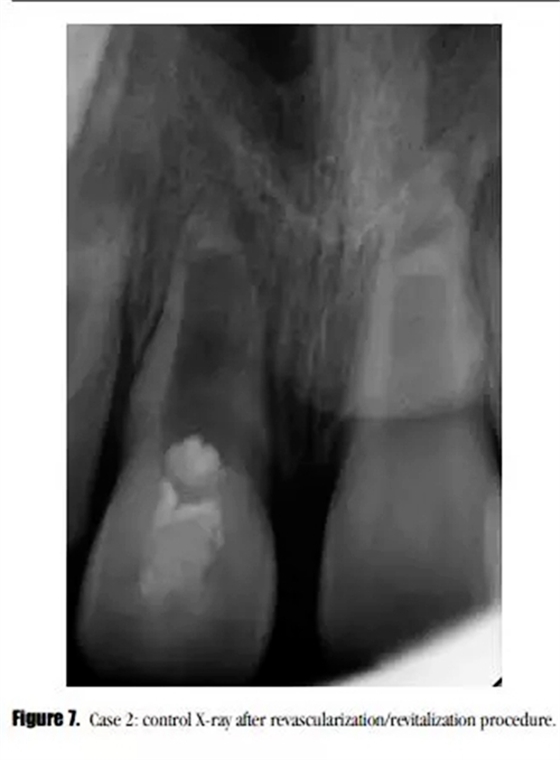

采用與之前所述一致的方法對患牙進行治療,患者癥狀消失。在初次就診之后的3個月后,我們開始了第二次治療。術后X線顯示,牙根進一步發(fā)育,沒有牙根根管壁的沉積,MTA塌陷進入到血凝塊中。(圖7)

盡管在3個月的隨訪中,瘺管沒有消失,但是牙齒的癥狀已經(jīng)消失了。X線顯示根尖區(qū)的進一步發(fā)育,牙根近中方向有透射性影響。與患者家長溝通后,1個月后實行常規(guī)根管治療。根尖區(qū)放置5mm后的MTA栓,復合樹脂以及纖維加強樁修復。少量的MTA從根尖近中方向被壓出。此外,根管系統(tǒng)以及繼發(fā)生成的根尖組織之間可見一明顯的透射影像。(圖8)